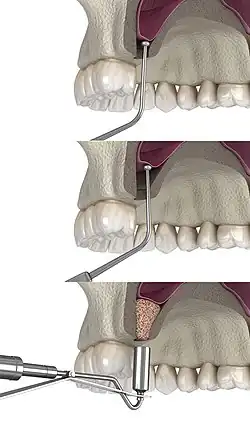

Osteotome technique

The osteotome method, developed by Hilt Tatum and later described by Robert B. Summers,[11] uses a transcrestal approach with osteotomes. It is less invasive but limited in augmentation. Implant survival remains high.[12]

Variations include the Localized Management of Sinus Floor (LMSF) technique[13] and use of electrical mallets to simplify transcrestal elevation.[14]